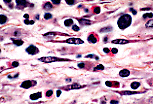

巨噬细胞

此为光镜下吞噬了淋巴细胞的巨噬细胞:核圆、居中、染色浅,胞质内可见被苏木精染成蓝黑色的包涵体,这些包涵体是含固缩淋巴细胞的溶酶体。 |